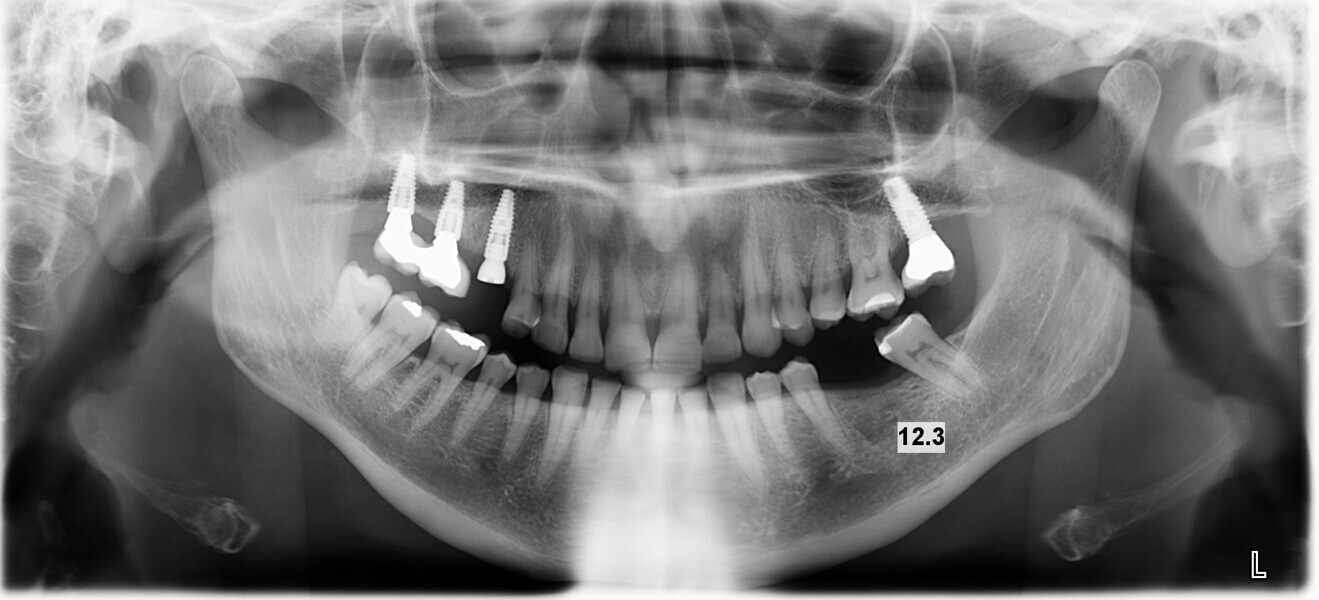

Conventional and immediate loading with final n!ce screw-retained crowns